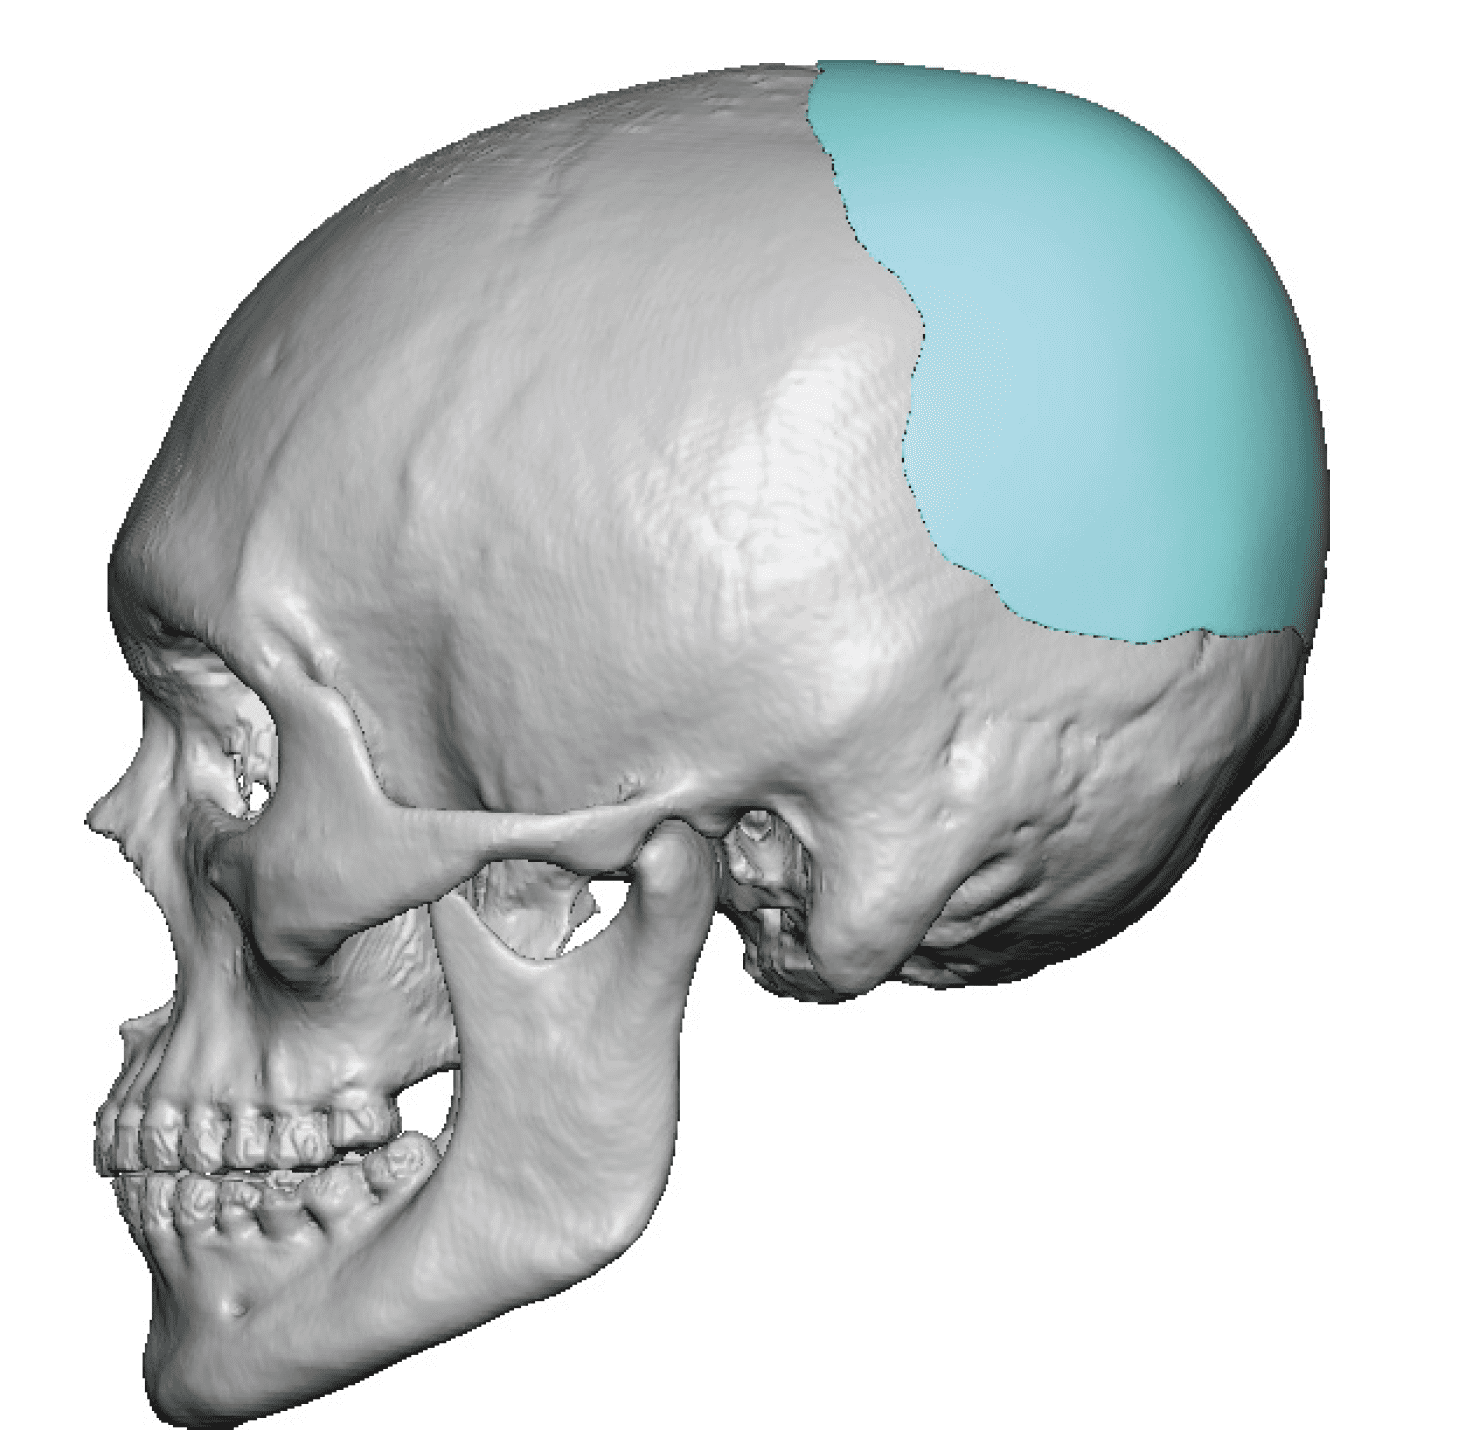

Desire for an improved head shape so that it looks rounder and not so peaked or sloped.

Placement of custom skull implant for parasagittal augmentation to create a rounder head shape. An example of what appears to be a high sagittal crest that is really low parasagittal skull areas.

Desire for an improved head shape so that it looks rounder and not so peaked or sloped.

Placement of custom skull implant for parasagittal augmentation to create a rounder head shape. An example of what appears to be a high sagittal crest that is really low parasagittal skull areas.